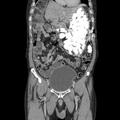

Nasploh zdravniki po svetu precej pogosto poročajo o "nenavadnih odkritjih" oziroma tujkih, ki so jih hote ali nehote zaužili odrasli. Tako smo pred tem pisali o podobnem primeru 54-letnega moškega iz Južne Koreje. Pri njem je je računalniška tomografija (CT) trebušnih organov pokazala, da je želodec napolnjen s tujki, natančneje s kovanci in kamenčki, ki so tehtali kar dva kilograma. Bolnik jih je goltal, ko je bil zaskrbljen, saj ga je takšno početje pomirilo.